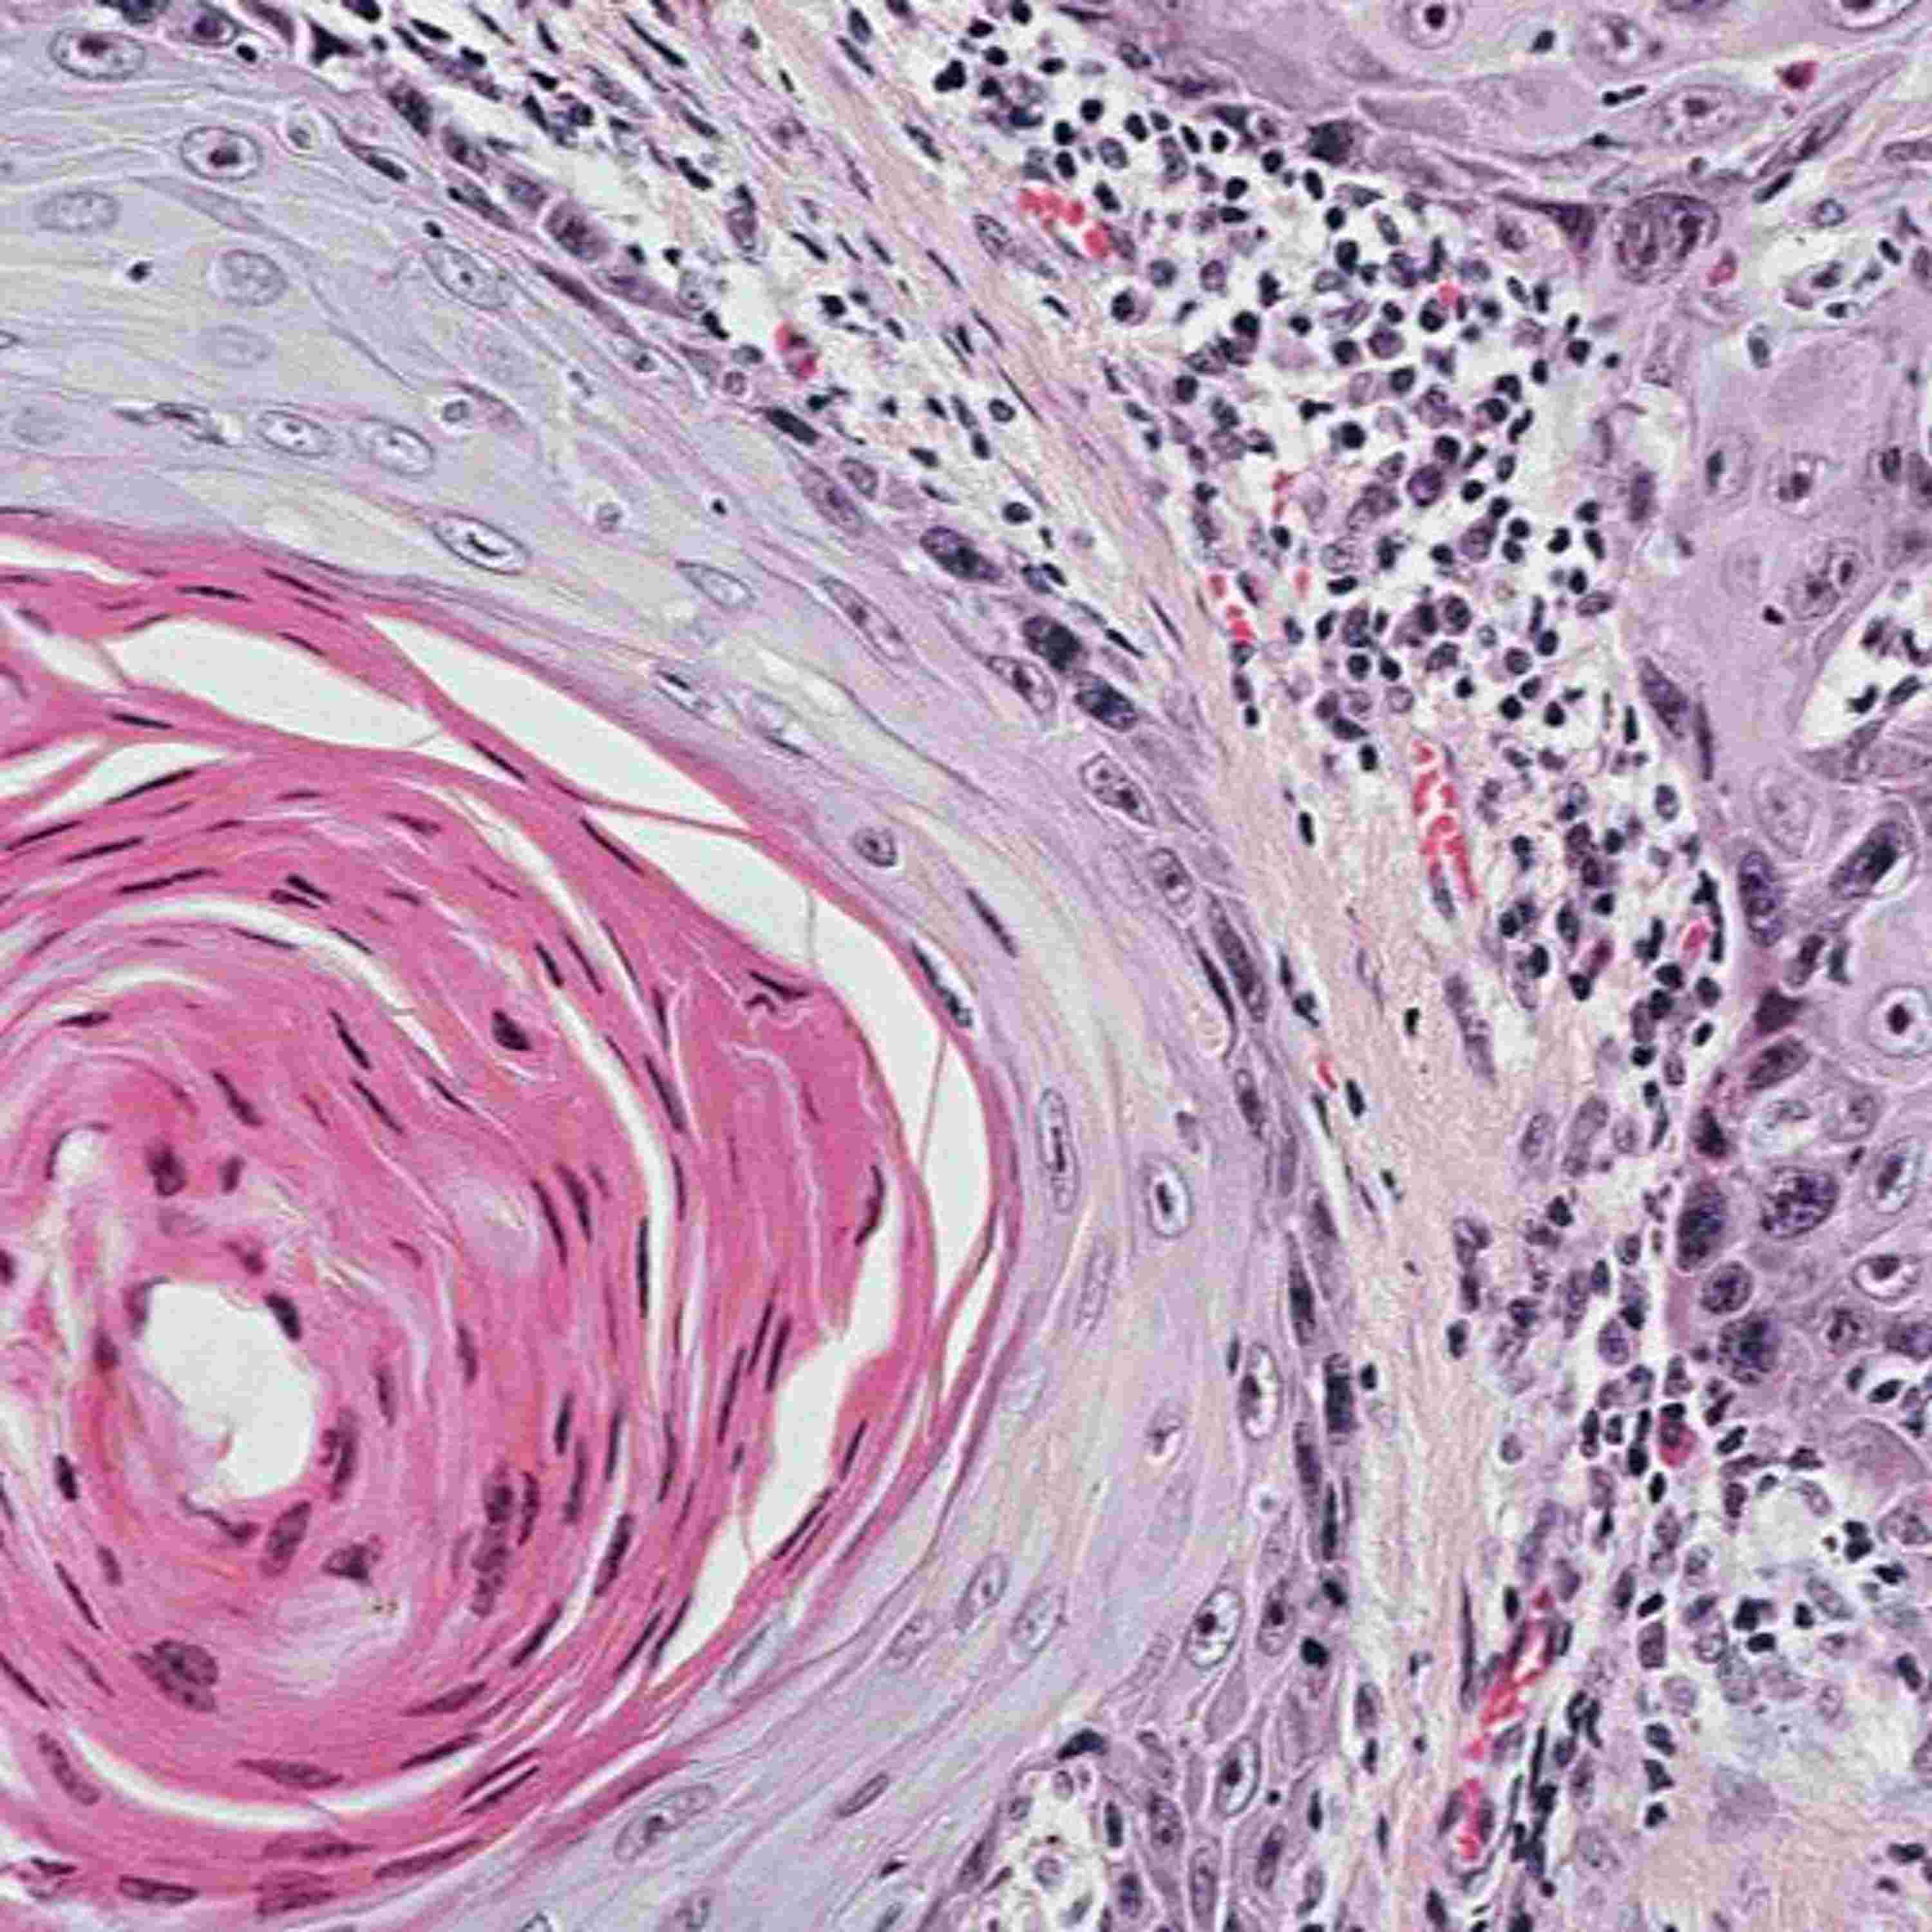

Episode 2 - Clinical-grade computational pathology

#Pathology is an essential step for cancer diagnosis. It is currently being revolutionized by #ArtificialIntelligence. We discuss the promises and challenges in digital pathology in our latest episode, available on SoundCloud, Apple Podcasts and Spotify. --------------------- Links to go further: The article: https://www.nature.com/articles/s41591-019-0508-1 What happens after a biopsy: https://www.cancer.net/navigating-cancer-care/diagnosing-cancer/reports-and-results/after-biopsy-making-diagnosis